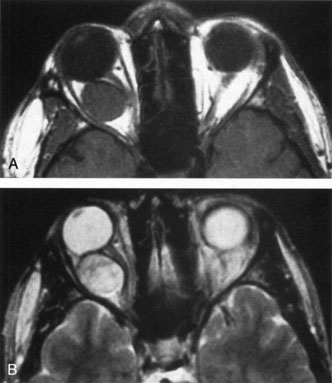

Fig. 10. A and B. No flow malformation of the orbit. Sagittal magnetic resonance imaging showing dilated cystic spaces hypointense to muscle on T1-weighted images (A) and hyperintense to muscle on T2-weighted images (B).